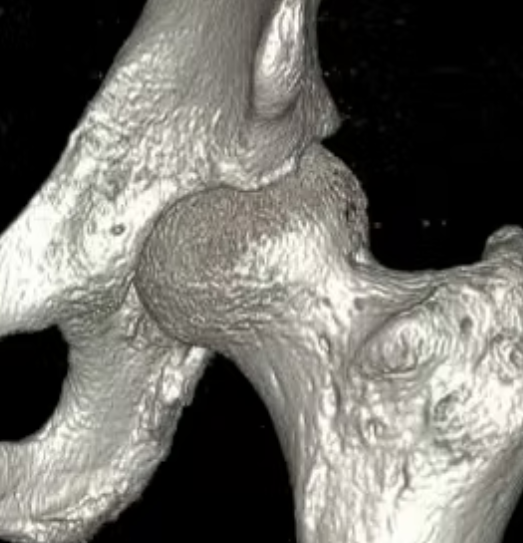

CT

Pincer

Focal pincer

Os acetabuli

Subspine impingement

Enlarged AIIS likely from old partial avulsion